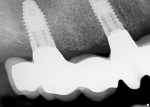

The zirconia implant bridge was seated in the patient’s mouth, and periapical films confirmed proper fit. Panorex radiographs demonstrated anatomical structures (Figure 12 and Figure 13). The crown and zirconia implant bridge screw access hole was filled with polyvinyl siloxane material (Figure 14). The crown was temporarily cemented in place using transparent temporary cement (Teliolink, Ivoclar Vivadent) while the abutment screws were torqued to 35 Ncm and covered with flowable composite (Tetric EvoFlow, Ivoclar Vivadent) (Figure 15). The composite was then light-cured (Demetron, Kerr Corporation, www.kerrdental.com).